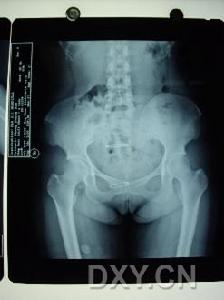

骶髂關節結核--影像檢查時在站立位脊柱前彎、後伸及側彎均受限,並有局部疼痛,但坐位時活動較好。臥位直腿抬高試驗,患側受限並有局部疼痛。壓擠或分離髂骨時患部疼痛,骶髂關節患部有壓痛,可有寒性膿腫或竇道。肛指檢查有時可摸到局部膿腫及壓痛。X線照片檢查對早期診斷很重要,需照骶髂關節正位及斜位(關節的矢狀面),可見骨質破壞、死骨及空洞形成等。

X線攝片早期關節面模糊,邊緣糜爛,關節間隙增寬,晚期關節間隙變窄。並有竇道,常繼發感染。關節呈現硬化。關節破壞嚴重者同側髂骨和恥骨可上移發生病理脫位。

患側分髖試驗和骨盆擠壓試驗常為陽性。